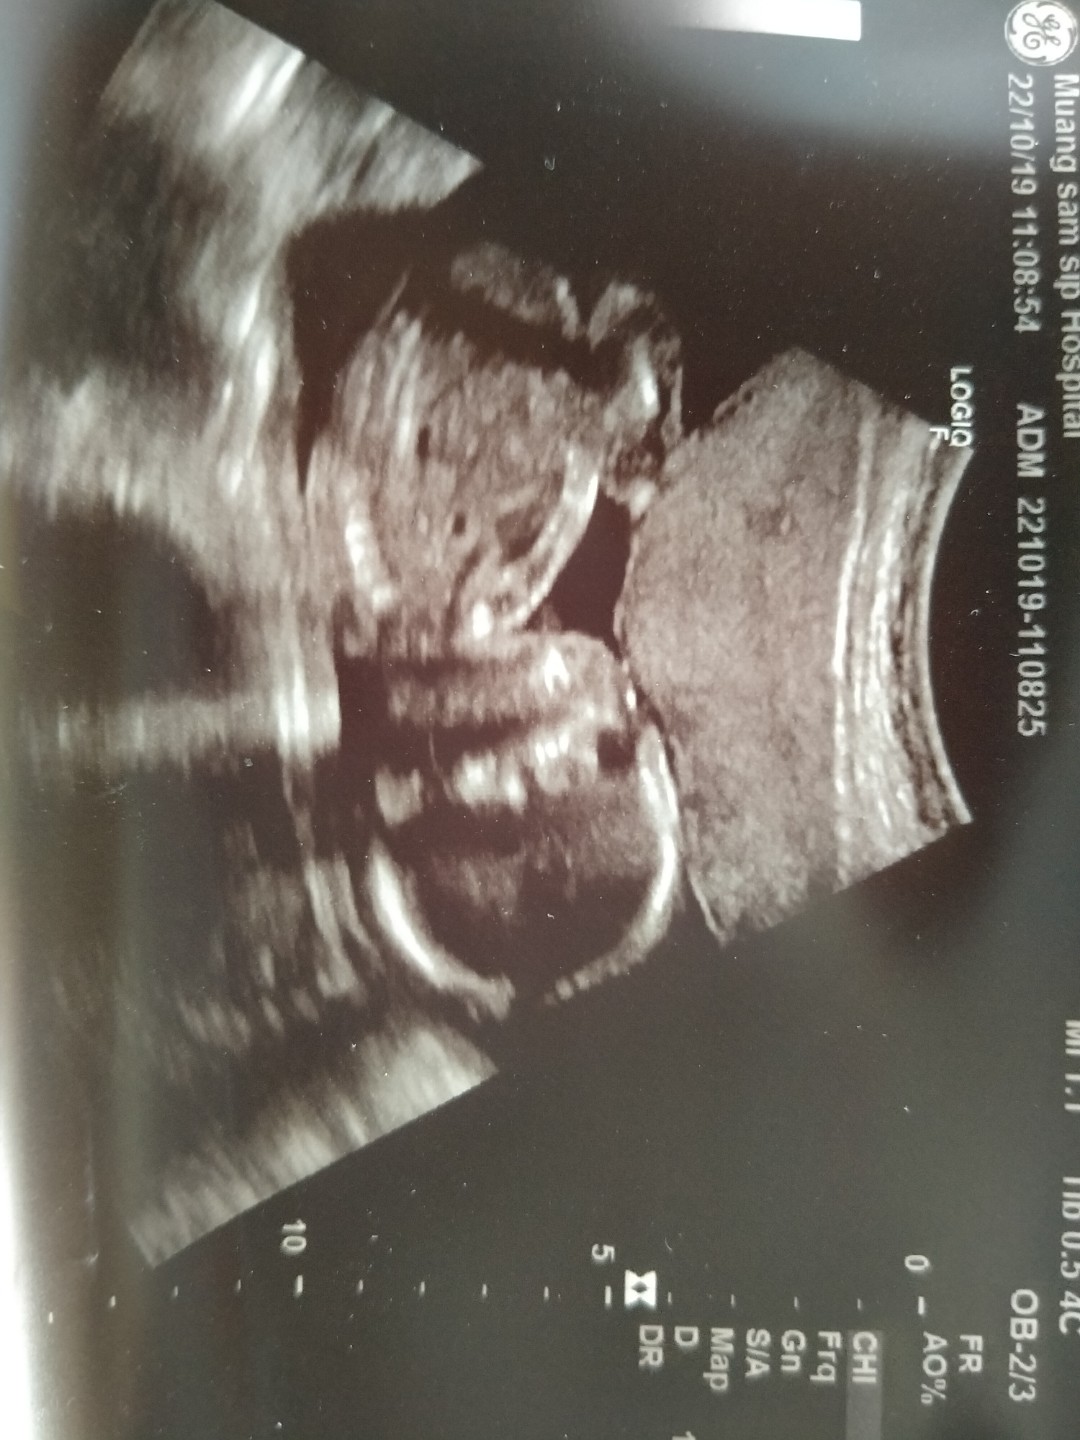

จู๋ชัดมากค่ะ..5เดือนแล้ว